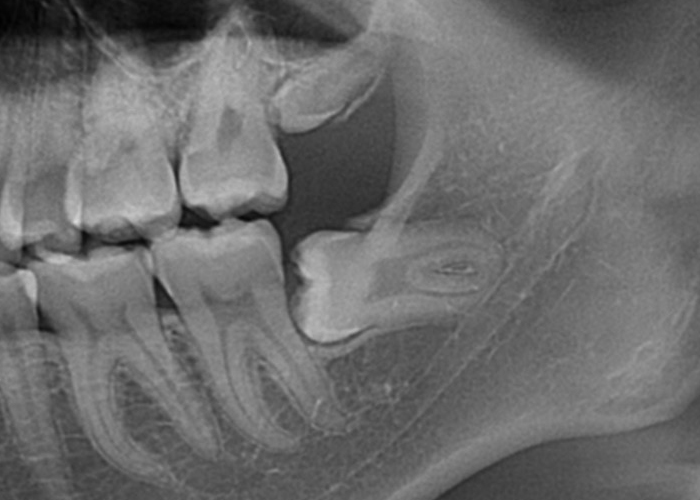

完全埋伏智歯(歯茎に完全に埋まっている)

完全埋伏とは、親知らずが完全に歯肉の下に完全に埋まっている状態を指します。

この場合、親知らずは通常、レントゲンやCTスキャンなどの画像検査でのみ確認できます。

完全埋伏の親知らずは、周囲の組織に直接的な問題を引き起こさない場合もありますが、将来的に問題を引き起こす可能性があります。

そのため、定期的な口腔検診や画像検査が重要です。